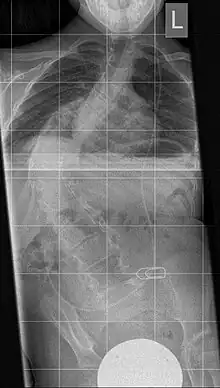

The instrument is used to dilate a too small or too narrow rib thorax in severe thoracic deformity. It consists of a telescopic "titanium rib" in curved form with several holes in a row for fixing in the desired length. A prolongation can be carried out after 6 months. The fixation takes place between two ribs or between a rib and the iliac crest. This results in an indirect erection of the deformed spine, resulting in an increase in the volume of the thoracic cavity along with the lung.